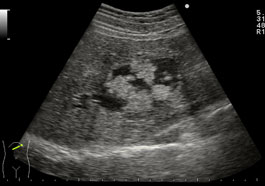

医師は画像検査や外科手術中に胆管過誤腫に似た腫瘍を発見することがあります。

診断を確定するために、詳しく調べるために画像検査を推奨する場合があります。これらのテストの例は次のとおりです。

場合によっては、これらの画像検査では、病変が癌性であるか非癌性であるかを判断するのに十分でない場合があります。このような場合、医師は予防措置として腫瘍を除去することを勧める場合があります。